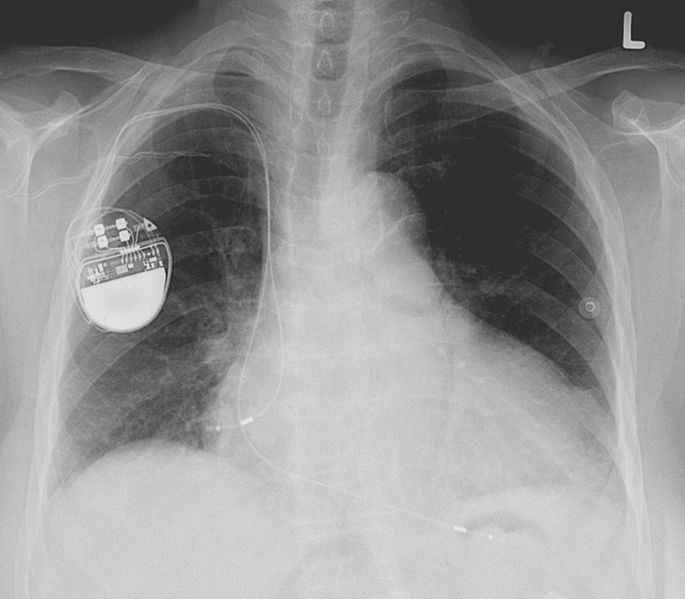

心臟節律器、植入式心臟去顫器(ICD)和其他帶有電子元件的假體通常會被移除,尤其是在火葬的情況下,因為它們含有可能發生爆炸的電池。 2002年的一項研究發現,「英國約有一半的火葬場曾發生心臟起搏器爆炸事件」。據報道,首例此類爆炸發生在1976年,在火葬場牆壁上炸出了一個「手指大小、半英寸深的洞」。 (死於火葬場心臟起搏器爆炸,這無疑是一種糟糕且頗具諷刺意味的死法。)

目前,歐美國家都禁止重複使用許多假體,例如心臟節律器。但這些設備價格昂貴,發展中國家的一些患者無力負擔新的設備費用。因此,一些慈善機構正嘗試重複使用這些設備。在英國,慈善機構 Pace4Life 收集可用的心臟節律器並將其送往印度。美國的一項名為「我的心,你的心」(Project My Heart Your Heart)的計畫也致力於在美國開展類似的工作,該計畫發現「75 名接受二手植入式心臟復律除顫器(ICD)的患者沒有出現感染或故障的跡象」。